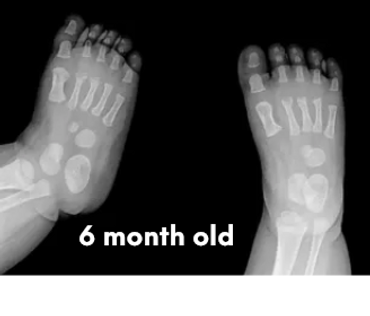

Babies’ feet are very soft and mostly made of cartilage in the first years of life. Their bones are still forming, and they have a thick layer of fat that makes their feet look chubby. This is why it’s important not to restrict their feet with tight or rigid shoes, as it could affect the natural shape and growth.

Let's check what their foot bones look like.

Pictures below will let you understand how babies' feet are developed.

Dear parents, children’s feet are developing structures, and the absence of an arch is a typical stage of development. The developing foot is not structurally ‘flat’; it is a highly compliant and plastic, that can respond to multiple factors, many of which we do not understand. Detailed X-RAY pictures above, let us understand that babies' foot bones are not connected till the teen years. Only at the age of 14, we may consider that the bones in the feet are developed and have reached their connections.